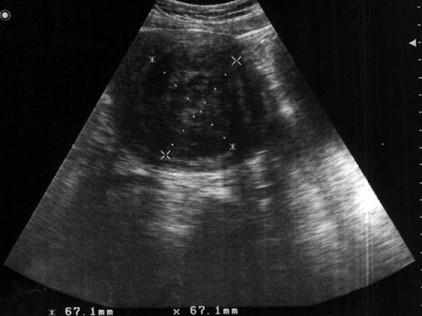

问题 患者女45岁,阴道不规则出血数月,妇检:子宫体积增大,如球形,B超检查声像图如图所示应诊断为 ( )

选项 A、子宫内膜Ca B、卵巢囊肿 C、子宫肌瘤 D、葡萄胎 E、卵巢Ca

答案 C